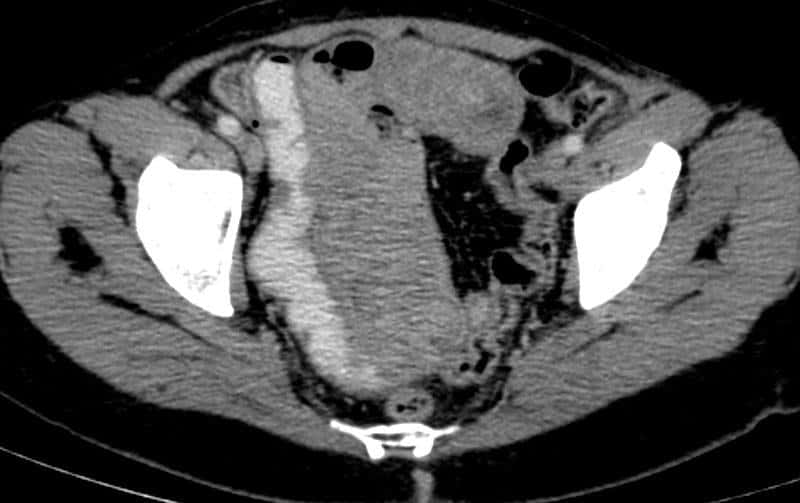

Di căn ruột non

» Thông tin: Nữ giới – 56 tuổi.

» Lâm sàng: Đau bụng.